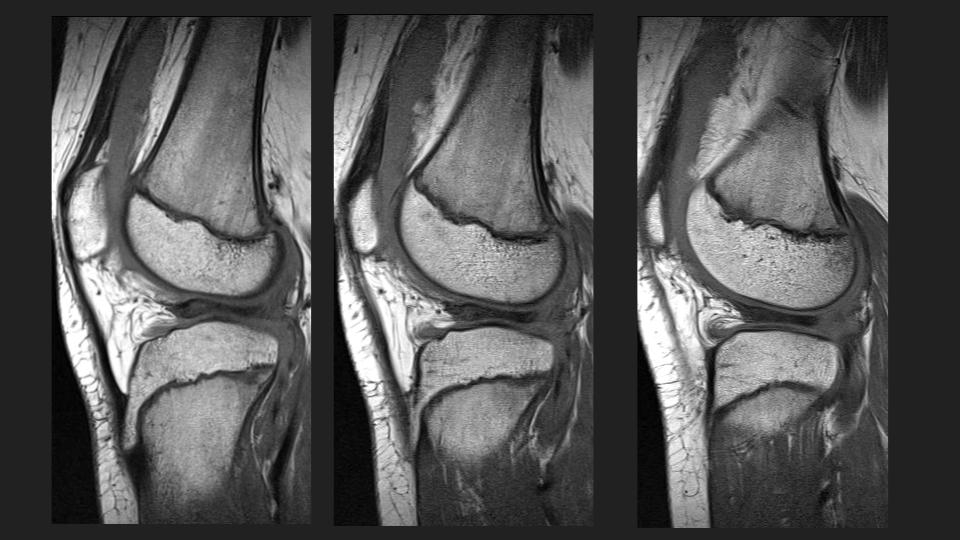

There is an anteriorly flipped bucket-handle type tear of a discoid lateral meniscus, which is not so interesting, until you see the prior MRI 16 months ago. At that time it appears that there was medial displacement of the posterior portion of the discoid LM, with thick irregular linear structures adjacent to the posterior horn region that I think were torn popliteomeniscal fascicles. Perhaps that predisposed to the current injury. The alternative possilbility is that this is a hypermobile discoid lateral meniscus, perhaps a Wrisberg variant. What do you think? Reference article.